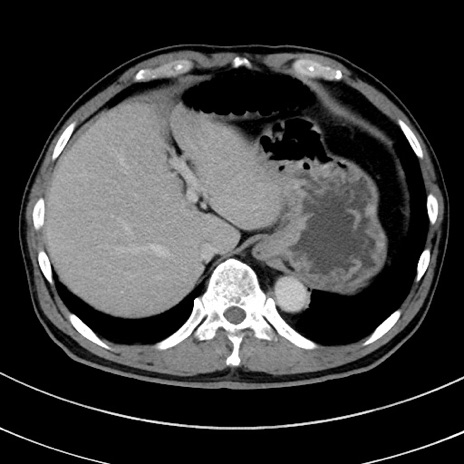

症例8(横断像)

【症例】 60歳代男性

【主訴】 黒色吐物

【現病歴】 4日前から嘔気自覚、2日前の朝食後にも嘔気あり、自分で手で嘔吐反射起こし嘔吐したところ血が混ざっていたため受診。

【既往歴】 5年前汎発性腹膜炎を伴う急性虫垂炎で手術、高血圧、前立腺肥大症、高脂血症

【身体所見】 腹部正中に手術癩痕あり 腹部平坦・軟圧痛なし膨満感あり

【データ】WBC 8400、CRP 4.54